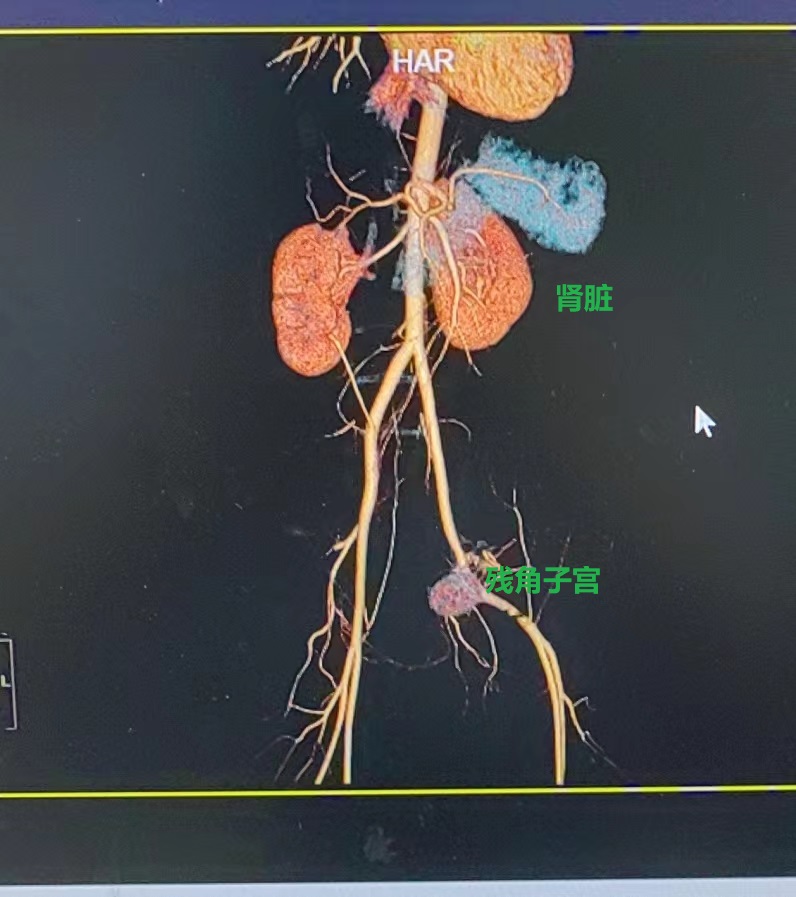

小红入院后,妇科团队立即给予抗感染等对症支持治疗,因其盆腔包块性质难以确诊,且为青春期少女,一旦误诊,切除了不该切除的器官,将对其今后的生活导致及其严重的打击,需详细制定诊疗方案。省人医帮扶专家、县人医副院长陈建国高度重视,立即与放射科组织开展病例讨论,根据三维CT血管成像,最终诊断残角子宫可能性大,小红有剧烈腹痛症状且有丰富血流,考虑为II型残角子宫,需行微创手术切除。

残角子宫为先天发育畸形,是一侧副中肾管发育不全所致,形成单角子宫。II型残角子宫有宫腔及内膜,与正常子宫不相通也可产生经血,但无法排出,从而导致周期性腹痛及残角子宫的宫腔内积血,经血逆流常导致子宫内膜异位症及卵巢巧克力囊肿。常合并有同侧肾脏输尿管发育异常等症状。

在征得小红及其家属同意后,5月25日,妇科团队为其在全麻下行腹腔镜联合宫腔镜探查,术中发现腹腔积血约100ml,盆腔内两个不相连的子宫,行腹腔镜下透光试验,确认左侧子宫为残角子宫,确认后再行腹腔镜下左侧残角子宫切除+左侧输卵管切除+左侧卵巢囊肿剔除术,手术非常顺利,术后在妇科团队的精心照料下,于5月31日痊愈出院。